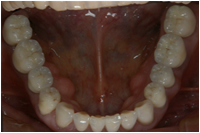

【審美総合:施術前】 【審美総合:施術後】

症例の説明

全体に歯並びが悪く、前歯は開いた状態で奥歯しか当たっていません。そのため奥歯の負担が大きくなり痛くてかめなくなっていました。

上顎の前歯、奥歯、下顎の奥歯にインプラントを埋めて、下顎の前歯は矯正治療を行い歯をよい位置に並べた後に全体をセラミックで治療しました。

きれいになったのはもちろん、良く噛める様になったとよろこんでいただきました。